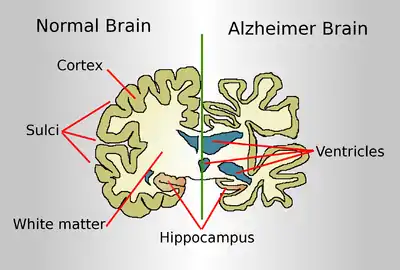

| Diagram of a normal brain compared to the brain of a person with Alzheimer's | |

The course of Alzheimer's is generally described in three stages, with a progressive pattern of cognitive and functional impairment.[27][20] The three stages are described as early or mild, middle or moderate, and late or severe.[27] The disease is known to target the hippocampus which is associated with memory, and this is responsible for the first symptoms of memory impairment. As the disease progresses so does the degree of memory impairment.[18]

Alzheimer's disease is characterised by loss of neurons and synapses in the cerebral cortex and certain subcortical regions. This loss results in gross atrophy of the affected regions, including degeneration in the temporal lobe and parietal lobe, and parts of the frontal cortex and cingulate gyrus.[84] Degeneration is also present in brainstem nuclei particularly the locus coeruleus in the pons.[85] Studies using MRI and PET have documented reductions in the size of specific brain regions in people with Alzheimer's disease as they progressed from mild cognitive impairment to Alzheimer's disease, and in comparison with similar images from healthy older adults.[86][87]

Both Aβ plaques and neurofibrillary tangles are clearly visible by microscopy in brains of those with Alzheimer's disease,[88] especially in the hippocampus.[89] However, Alzheimer's disease may occur without neurofibrillary tangles in the neocortex.[90] Plaques are dense, mostly insoluble deposits of beta-amyloid peptide and cellular material outside and around neurons. Tangles (neurofibrillary tangles) are aggregates of the microtubule-associated protein tau which has become hyperphosphorylated and accumulate inside the cells themselves. Although many older individuals develop some plaques and tangles as a consequence of aging, the brains of people with Alzheimer's disease have a greater number of them in specific brain regions such as the temporal lobe.[91] Lewy bodies are not rare in the brains of people with Alzheimer's disease.[92]